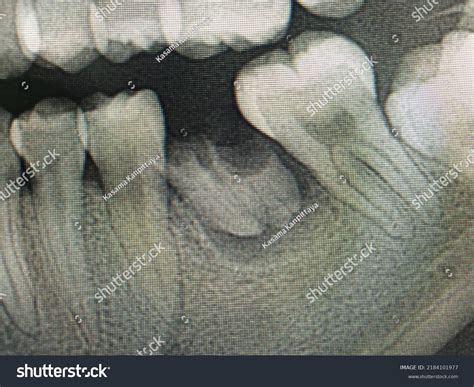

• Diagnosing Impacted Teeth: To determine the exact position of wisdom teeth or other teeth that haven't fully erupted.

When you visit your dentist for a toothache or a routine check-up, they may recommend a specific type of dental imaging to get a clearer picture of your oral health. Among the various diagnostic tools available in modern dentistry, the Periapical X Ray stands out as an essential imaging technique. Unlike broader panoramic X-rays that capture the entire jaw, a periapical image focuses on one or two specific teeth, providing an incredibly detailed view of the tooth from the crown down to the very tip of the root and the surrounding bone structure. Understanding what this procedure entails can help alleviate any anxiety you might feel about your upcoming dental appointment.

A Periapical X Ray, often referred to simply as a "PA," is a close-up, high-resolution diagnostic image. The term "periapical" literally translates to "around the apex," with the apex being the tip of the tooth root. This specific type of X-ray is designed to show the entirety of the tooth—from the biting surface (crown) down to the root end—as well as the surrounding supporting bone.